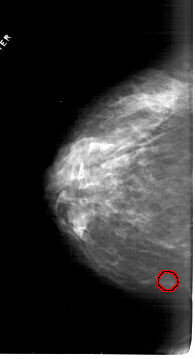

A_1814_1.RIGHT_CC

RIGHT_CC LINES 6316 PIXELS_PER_LINE 3811 BITS_PER_PIXEL 12 RESOLUTION 43.5 NON_OVERLAY